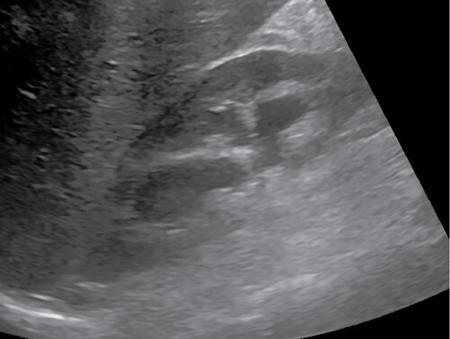

Pyonephrosis is accumulation of pus in an obstructed pelvicalyceal system with suppurative destruction of the renal parenchyma. It is a medical emergency and early recognition of this condition is critical, as emergent decompression is needed to prevent rapid decline in renal function. In a patient with known obstructive uropathy, fever and flank plain should raise a red flag for possible pyonephrosis. There are a variety of causes of urinary obstruction (summarized in Fig. 10.12.2.4.9) and may be due to ureteric calculi, stricture, developmental ureteric anomalies, retroperitoneal fibrosis or malignant disease. End-stage chronic pyelonephritis may also result in pyonephrotic kidney. Plain X-ray abdomen may show enlarged kidney with or without stones. Intravenous Urogram shows poorly or nonfunctioning kidney. It is often the first diagnostic imaging study, demonstrating dilated collecting system with dependent echoes and shifting debris representing purulent inflammatory contents, which helps to distinguish this condition from simple hydronephrosis (Fig. 10.12.2.4.10). The echogenic debris may appear mass like, thus confusing with haemorrhage or tumour; however avascularity on Doppler interrogation suggests pyonephrosis.